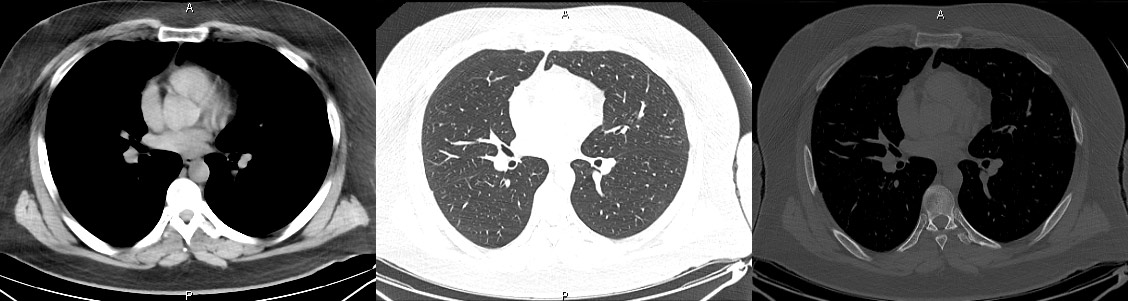

Obținerea de imagini ne-suprapuse ale corpului uman, imaginile obținute sunt “felii” (slice-uri) transversale prin corp, de diferite grosimi, obținute prin iradierea și captarea imaginilor din diferite unghiuri (practic, tubul Röntgen se rotește în jurul corpului 360 de grade și îl “fotografiază” din toate unghiurile). În linii mari, am putea spune că o computer tomografie este la baza o radiografie din toate unghiurile. De fapt, calcule complexe determină atenuarea razei X (cât de mult sau cât de puțin este absorbită radiația printr-o regiune) pentru fiecare regiune din corp și apoi computerul, pe baza complexului aparat matematic din spate, atribuie o imagine în nuanțe de gri fiecărei felii de imagine. Prin urmare, spre deosebire de radiografie care este o imagine directă (radiația care trece prin corpul uman impresionează filmul), computer tomografia este o imagine reconstruită/calculată de computer. Din acest motiv, progresele matematice și fizice aduc îmbunătățiri permanente acestei tehnologii.

Introducerea tehnicii de achiziție spirală, care a permis achiziția continuă și rapidă a unui volum de date uriaș, cu posibilitatea de reconstrucție ulterioară în orice plan, nu doar cel transversal, precum și cu posibilitatea de reconstrucții tridimensionale spectaculoase. Inițial, achiziția se făcea doar în modul secvențial: după o rotație de 360 de grade a tubului, masa cu pacientul avansa în interiorulul aparatului cu grosimea unui slice (de obicei 10mm) și se făcea o noua achiziție. Acest mod este mai lent și nu permite reconstrucții în alt plan la fel de ușor ca achiziția spirală, la care tubul se învârte continuu, iar masa se mișca și ea în același timp. În prezent, achiziția secvențială se mai utilizează de rutină numai la examinarea cerebrală.

Creșterea vitezei de achiziție a imaginilor, în prezent putem obține imaginea statică a inimii (întreaga inima văzută într-o singură bătaie de inimă). Se obțin secvențe din ce în ce mai fine, slice-ri cu grosime de 0.5-1mm și rezoluții geometrice din ce în ce mai mari.